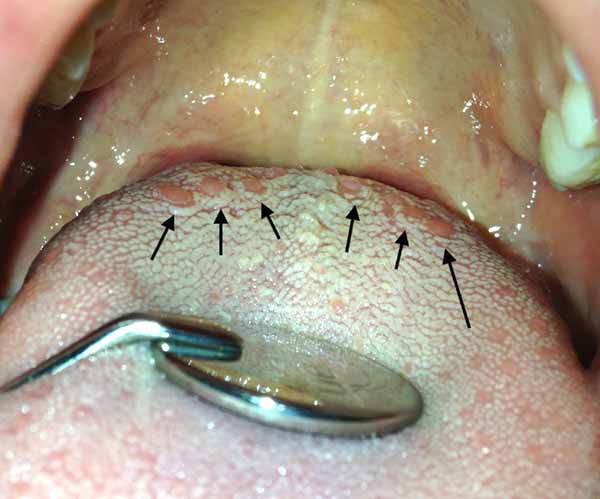

Papilla circumvallate isimli papillalar resimde ok ile isaretlidir ve aci tadi almakla görevlidir.

Dokunun su çekmesine veya uyarilmasina bagli olarak her gün ve hatta saat farkli renk ve büyüklükte izlenir. Bu çok normaldir

Bu papillalar herkeste bulunur. hastalik degildir.

Pas hariç ben bu dilde bir hastalik veya problem görmüyorum. Her yerde renk ayni, simetri saglam, kivam yerinde, her yer islak, renk bozulmasi yok, papil yükseklikleri her yerde homojen. Saglikli dil böyle olur.

Belki bu dil firçalanirsa iyi olur, yüzeydeki pas kaybolur.